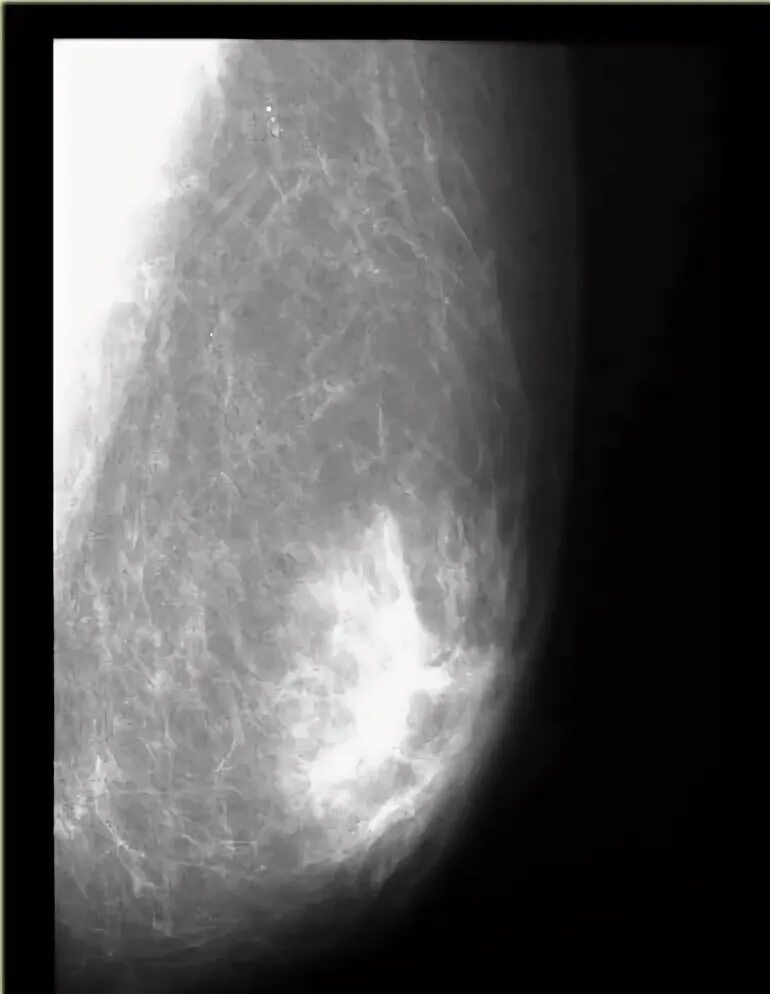

Диффузный аденоз